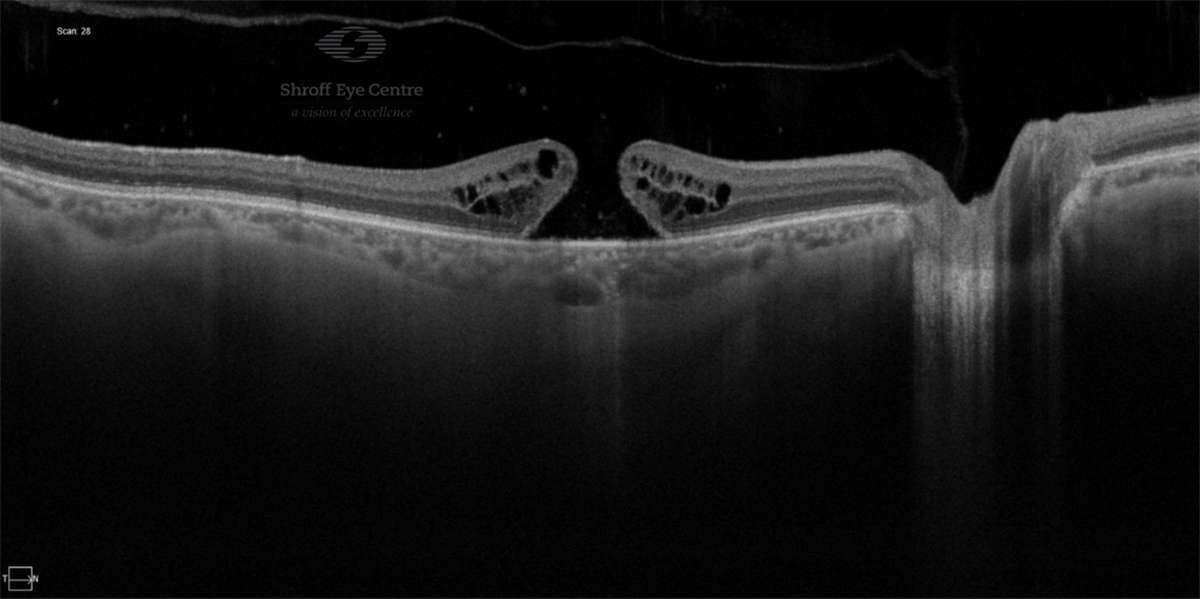

Diagnosis of retinal hole

A comprehensive retina check and examination by binocular indirect ophthalmoscopy is the only way holes in the retina or tears may be detected before they can cause retinal detachment. OCT may also be done to document and analyse the retina.